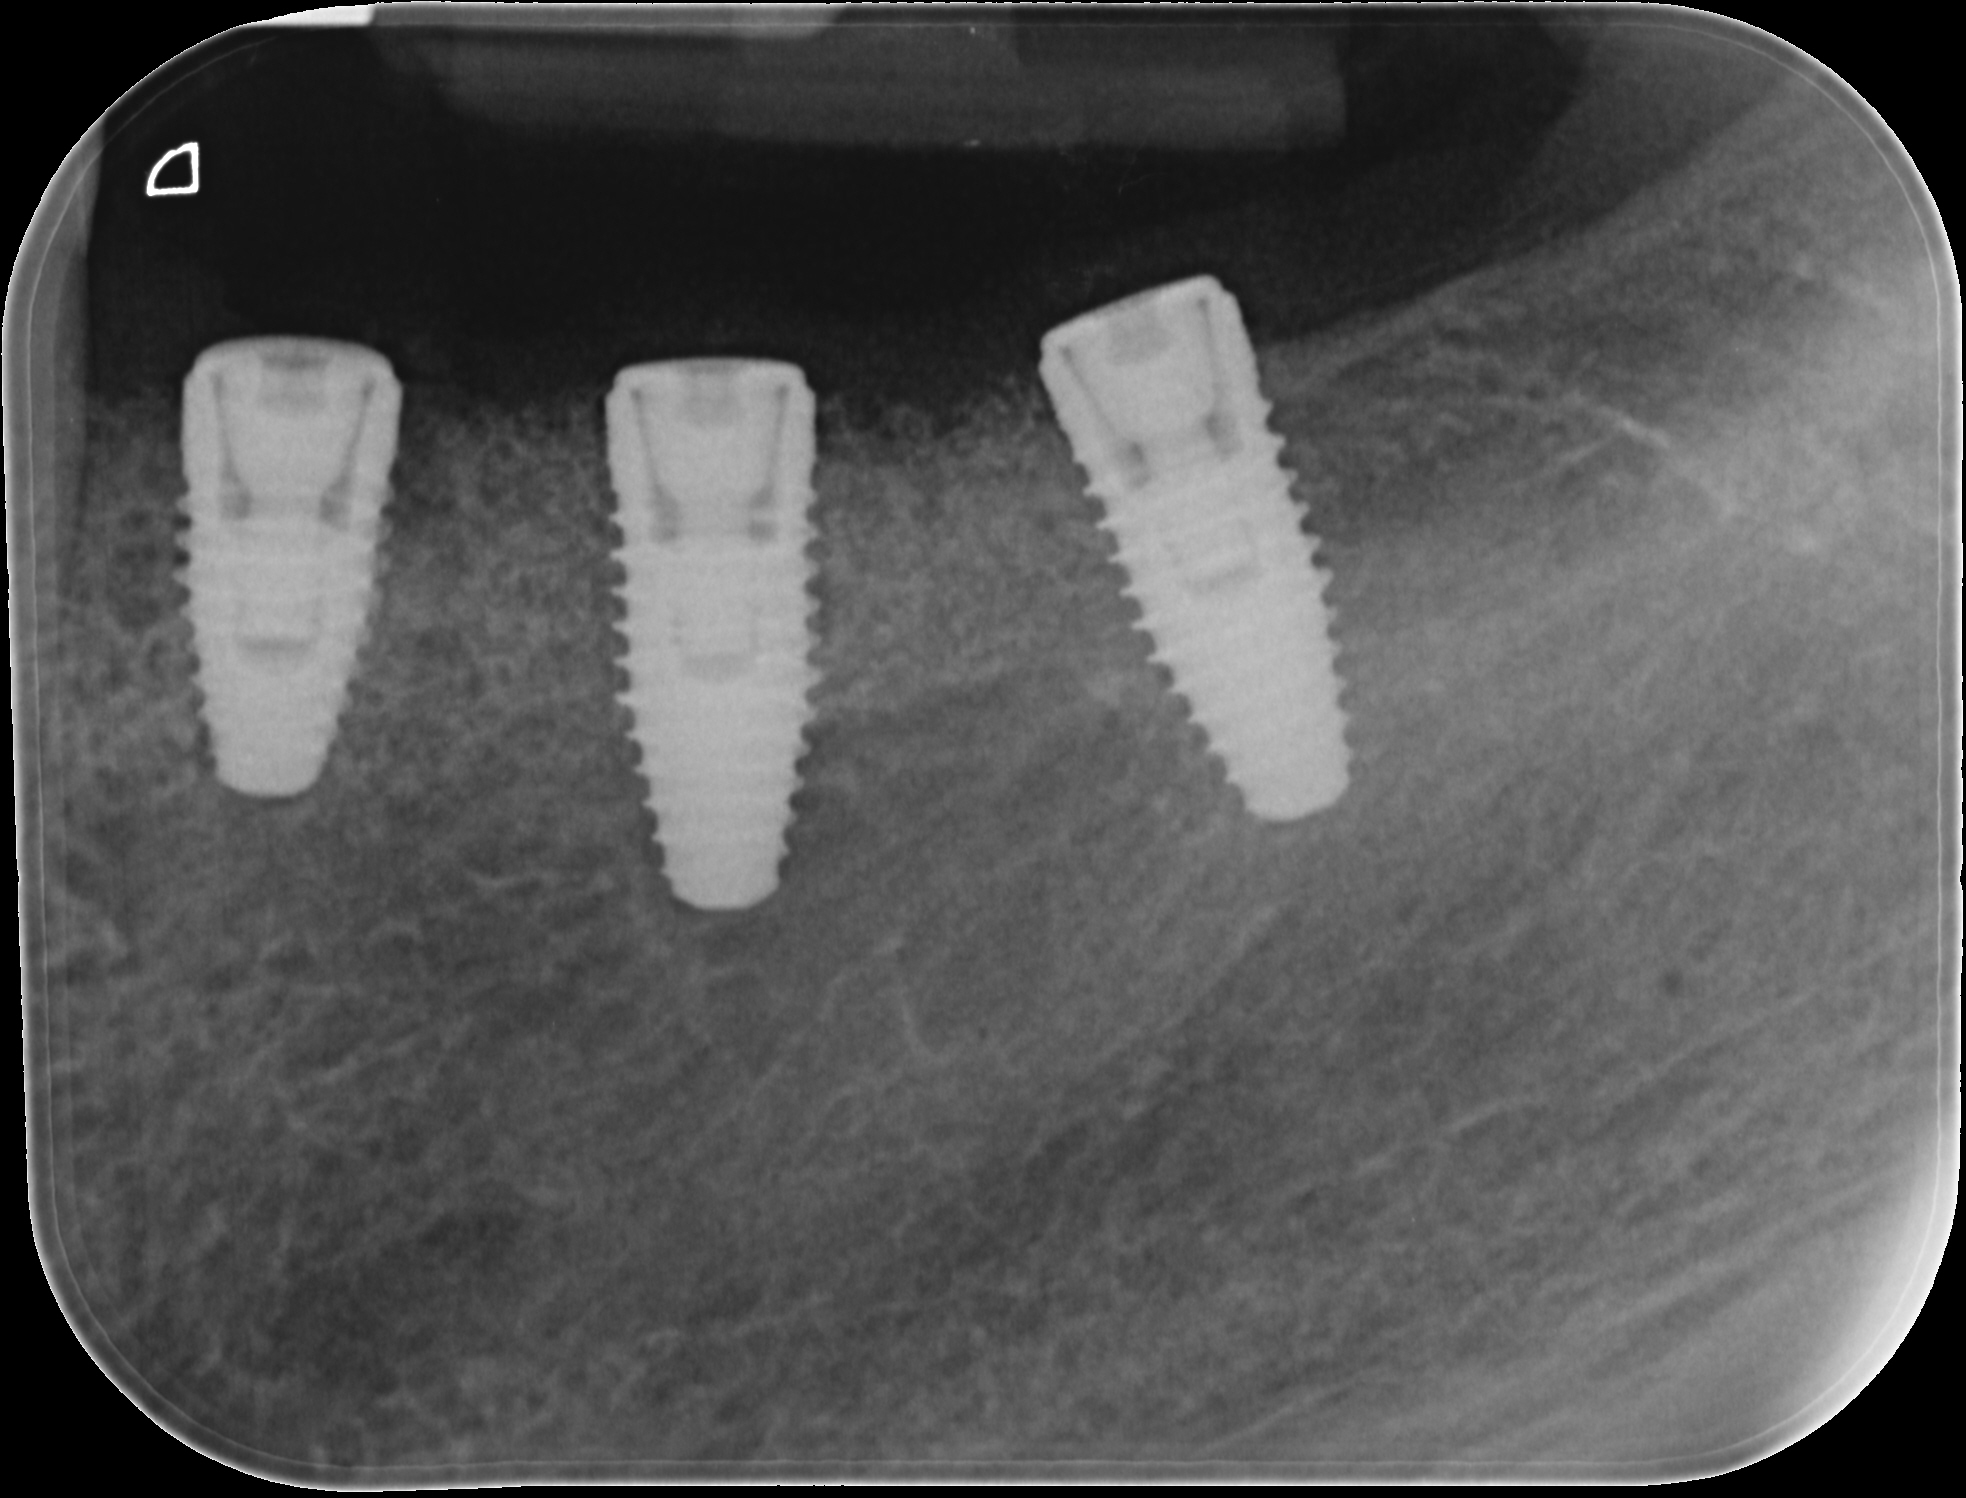

Replacement of a fixed partial denture with three implants

A 52-year-old patient is a referral and has been wearing an immediate provisional partial denture after replacement of her worn and fractured fixed partial denture. As a definitive treatment solution, the patient desired "beautiful and long-lasting" implant-supported single crowns. Clinically the CT-scan revealed a very narrow bone crest ("knife-edge") in the 3rd quadrant. Implant placement has been planned with a simultaneous GBR procedure.